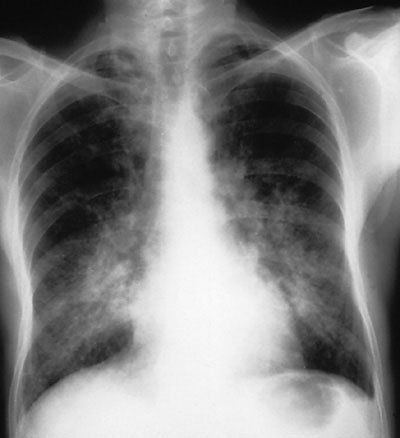

Xuất huyết phế nang lan tỏa và vô căn

Có hai loại xuất huyết phế nang thường gặp là xuất huyết phế nang lan tỏa và xuất huyết phế nang vô căn. Biểu hiện lâm sàng là tình trạng ho ra máu hoặc một số trường hợp chảy máu rỉ rả và hình thành các cục máu đông trong lòng phế nang, gây cản trở quá trình trao đổi khí, ảnh hưởng đến tính mạng của người bệnh.